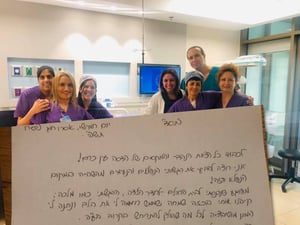

מיוחד: החוויה של לידה ראשונה בצל הקורונה

לידה בלי מלווים, אשפוז משונה וברית בזום, מה עובר על היולדות בצל הקורונה? מיכל, חברתה של האחות והבלוגרית, גילי בן נעים, שילדה לפני מספר שבועות בצל הקורונה, שיתפה אותה בחוויות השונות והמשונות (לידה)

| גילי בן נעים |